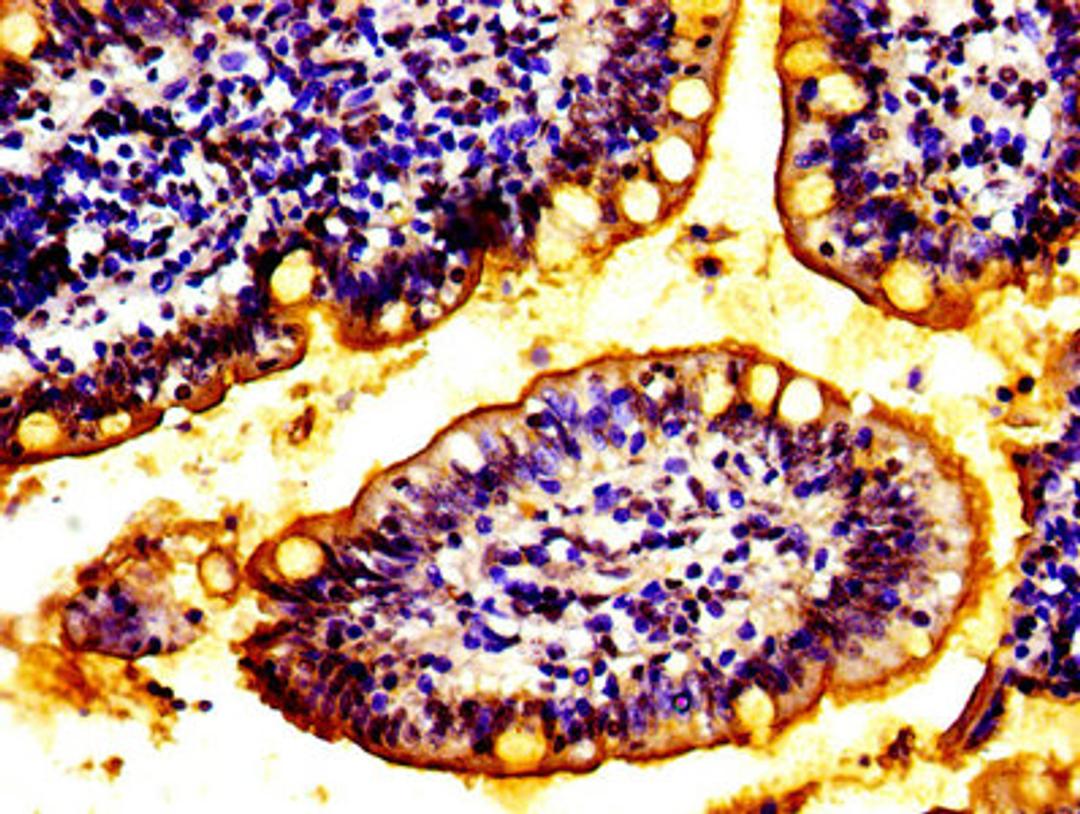

IHC image of CSB-PA873704LA01HU diluted at 1:100 and staining in paraffin-embedded human small intestine tissue performed on a Leica BondTM system. After dewaxing and hydration, antigen retrieval was mediated by high pressure in a citrate buffer (pH 6.0). Section was blocked with 10% normal goat serum 30min at RT. Then primary antibody (1% BSA) was incubated at 4°C overnight. The primary is detected by a biotinylated secondary antibody and visualized using an HRP conjugated SP system.